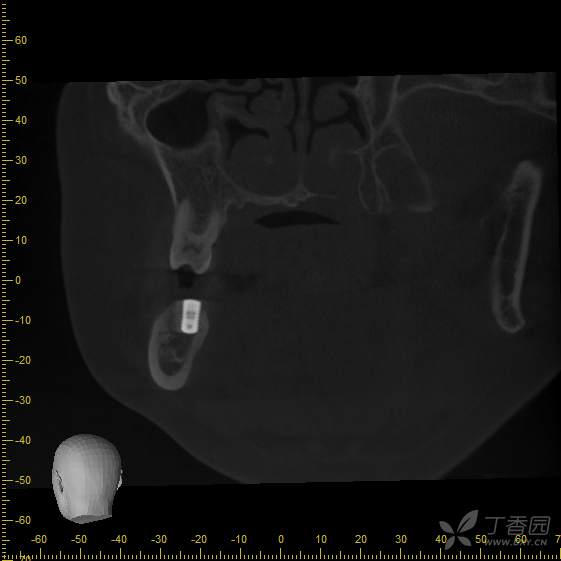

接诊时,36种植牙松1-2°,颊侧牙龈未见明显红肿。拍摄cbct后可见种植体周骨结合丧失,大量低密度影,骨吸收至根尖1/3,种植体浮出。